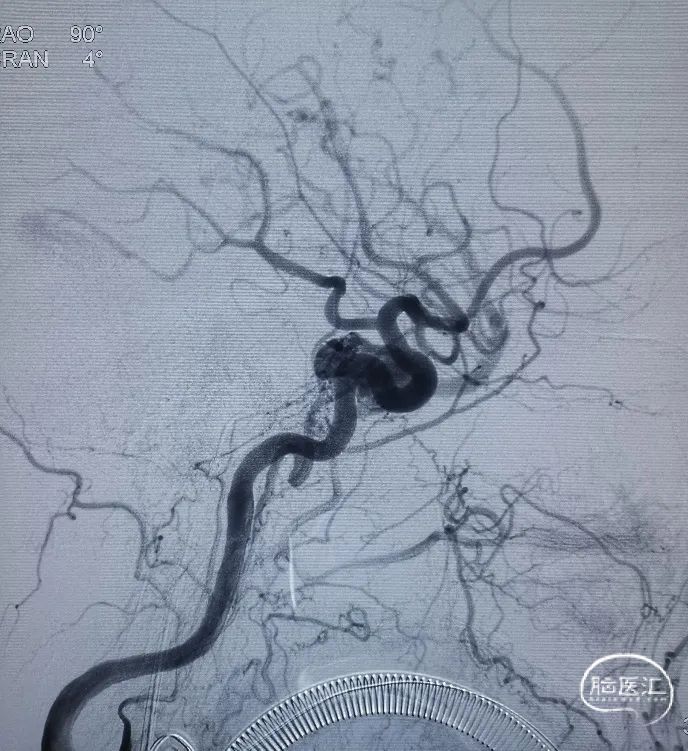

术前造影。

右侧海绵窦硬脑膜动静脉瘘:

· 供血动脉:双侧颈内及颈外动脉分支

· 引流静脉:右蝶顶窦-侧裂静脉-(Trolard静脉-上矢状窦/Labbe静脉-右侧横窦)

· 分型:Barrow D型、Corgnard III型、Borden III型

在Roadmap下,用泥鳅导丝开通右侧岩下窦,泥鳅导丝成功超选至右侧海绵窦内。

造影证实泥鳅导丝位置。

在Roadmap下,用0.014" 微导丝携第1根Echelon-10微导管超选通过开通的岩下窦进入海绵窦内,远端位于瘘口附近,微量造影证实微导管位置。

然后撤出泥鳅导丝,在Roadmap下,用0.014" 微导丝携第2根Echelon-10微导管超选通过开通的岩下窦进入海绵窦内,在3D造影辅助下选取工作角度,将第2根Echelon-10微导管成功超选至右侧蝶顶窦开口处,微量造影证实微导管位置。

调整第2根Echelon-10微导管位置后,先向蝶顶窦开口处填入Jasper®弹簧圈。

然后通过第1根微导管向瘘口处海绵窦注射Onyx栓塞剂。注射过程中通过造影导管在左侧颈外动脉反复造影,直至该海绵窦硬脑膜动静脉瘘完全不显影。最后做双侧颈总动脉造影,见右侧海绵窦硬脑膜动静脉瘘完全不显影,双侧颈内动脉、大脑中动脉、大脑前动脉及其它分支显影良好。行CT示颅内未见明显出血。